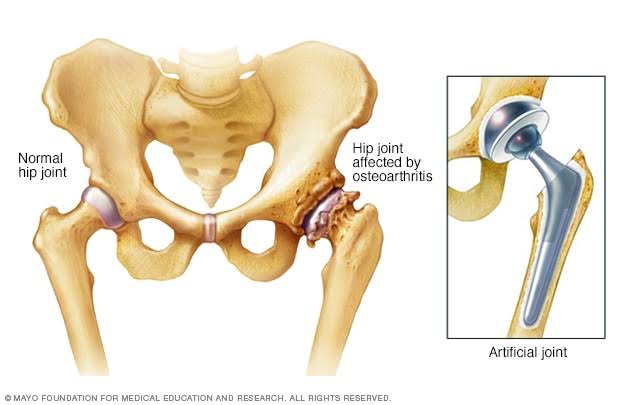

Una prótesis de cadera, o artroplastia de cadera, es una cirugía que reemplaza una articulación de cadera enferma o lesionada por una articulación artificial o un implante. Las personas suelen recibir reemplazos de cadera cuando la artritis causa dolor e inflamación de cadera severa. La fractura de cadera y el desgaste natural también son razones comunes para la cirugía de reemplazo de cadera.

Prótesis Total de Cadera

El reemplazo total de cadera es la cirugía de cadera más común. Utiliza componentes artificiales para reemplazar toda la estructura de la cadera. Durante el procedimiento, los cirujanos insertan un vástago en el fémur o el hueso del muslo del paciente para darle estabilidad. Reemplazan la cabeza del fémur con una bola y reemplazan la cavidad natural de la articulación de la cadera con una copa artificial.